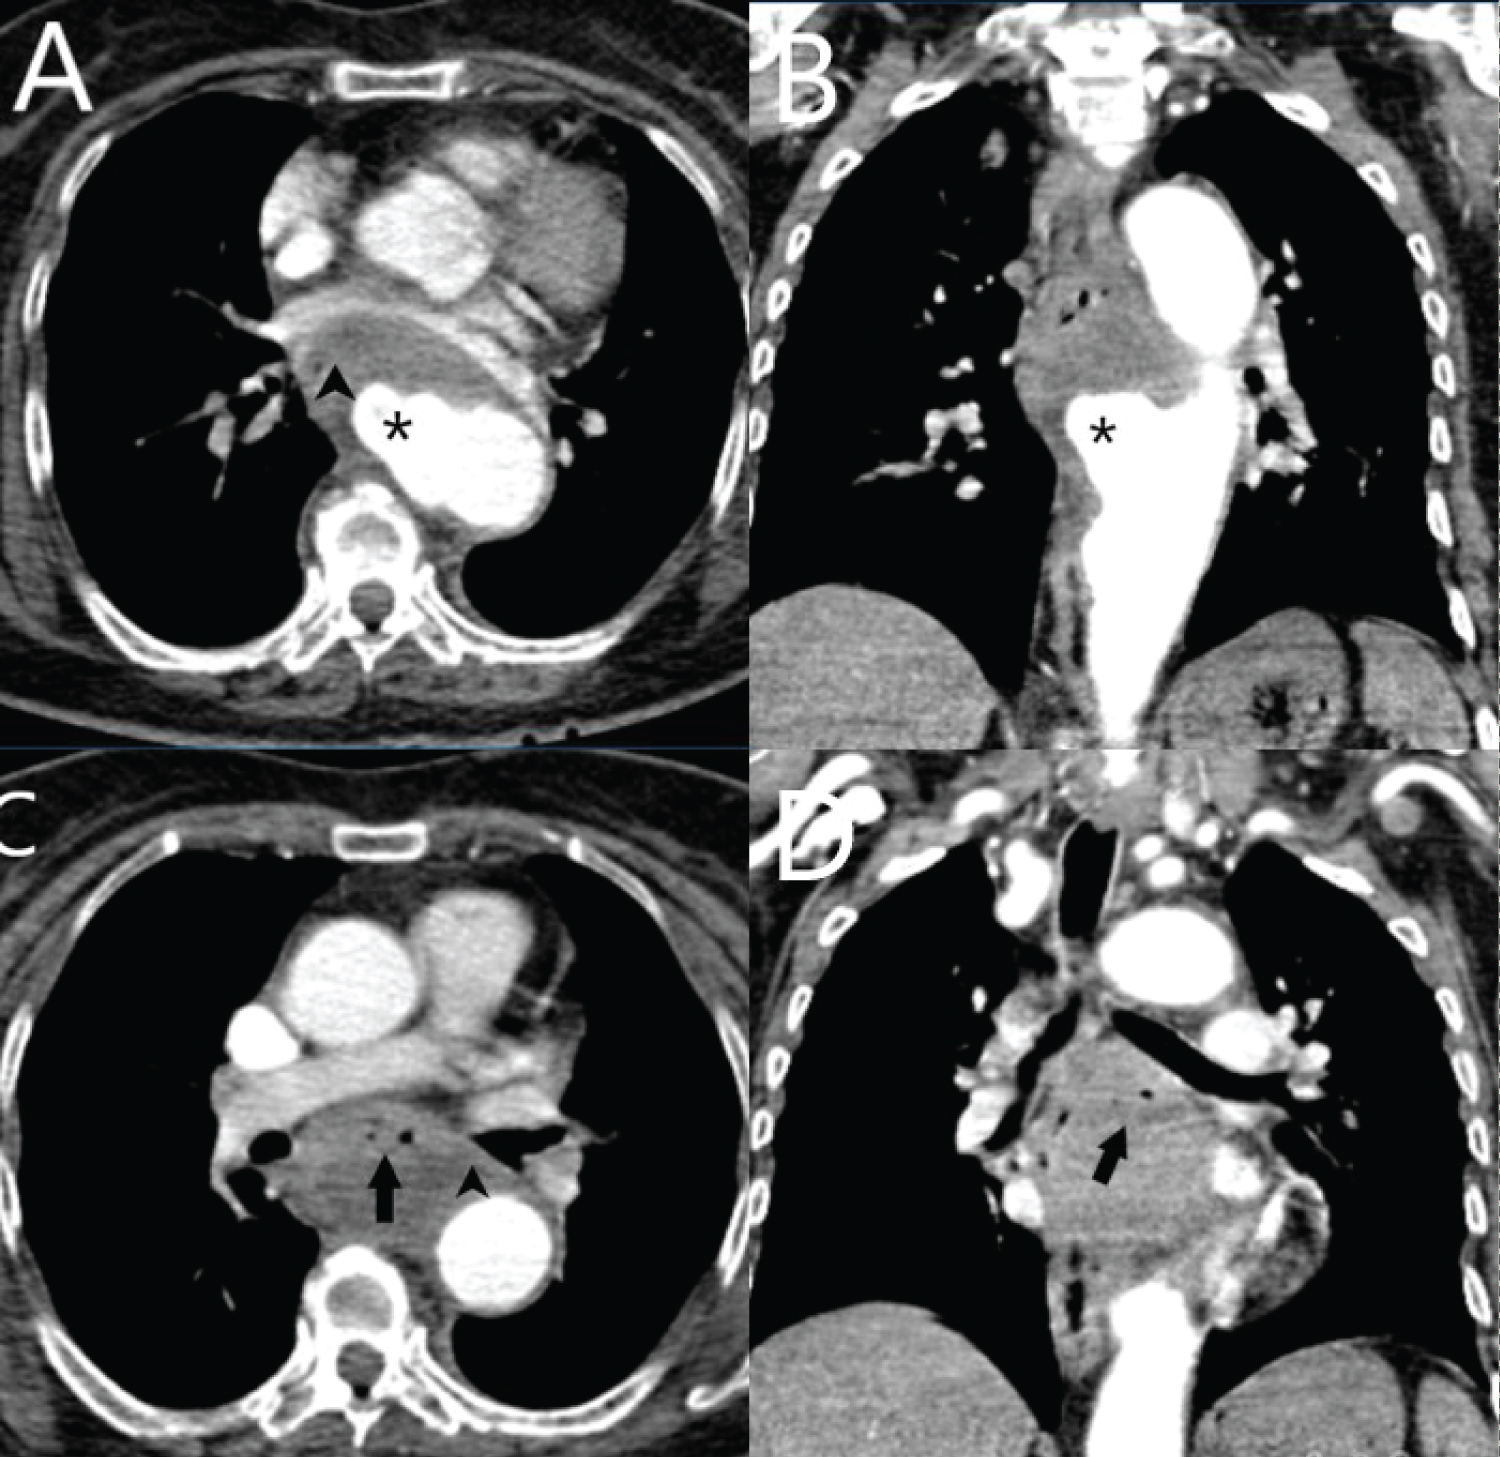

A Computed Tomography Angiography (CTA) was performed, revealing the presence of a saccular aneurysm in the thoracic aorta (Figure 1A and Figure 1B, asterisk). The observation of ectopic gas adjacent to the aneurysmatic aorta supported the diagnosis of AEF. Further more, the CTA showed evidence of aortic aneurysm rupture in to the esophagus, as well as the presence of air bubbles with in the mural thrombus (Figure 1C and Figure 1D, arrow).

Additionally, an indirect finding of AEF was noted with a disrupted aortic fat pad (Figure 1A and Figure 1C, arrowhead). Unfortunately, due to hemodynamic instability, the patient's condition deteriorated rapidly, and emergency curative surgery was planned. However, the patient passed away before the procedure could be performed.

Figure 1: The axial images of the Computed Tomography Angiography (CTA) are presented as A and C, while the coronal images are displayed as B and D.